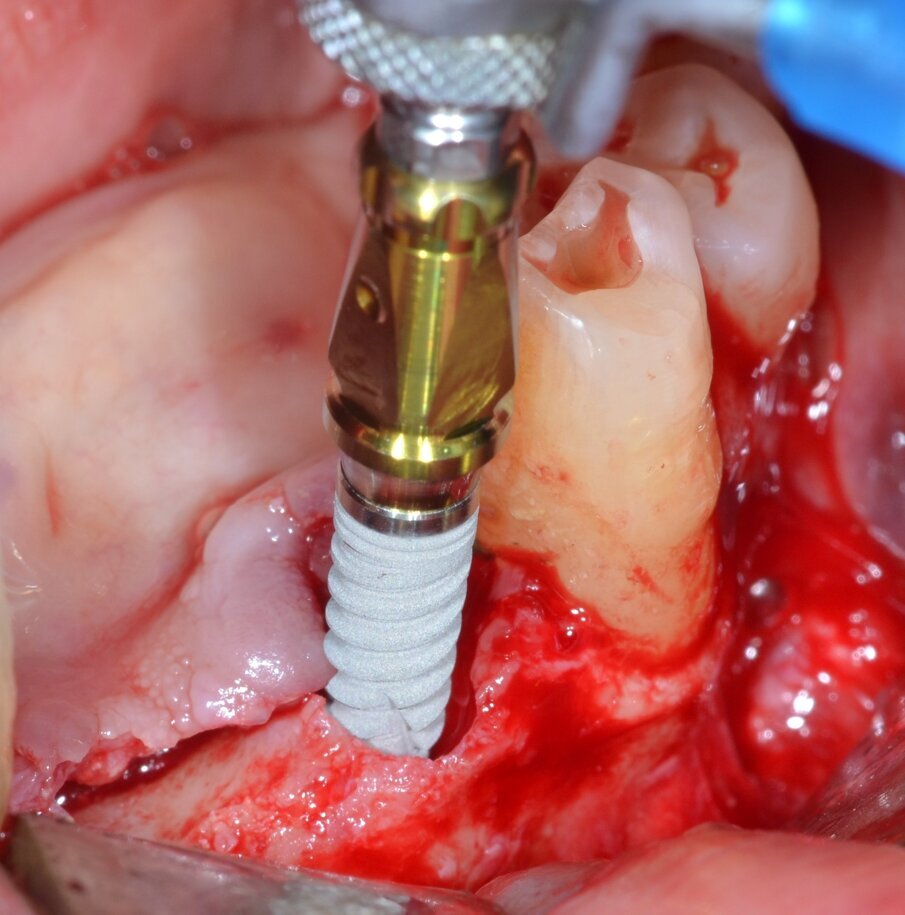

Sulla scorta dei dati ottenuti dalla simulazione effettuata con software Real Guide Ver. 5.0 (3Diemme, Como) si procede all’inserimento di quattro impianti endossei misura 3,5x13 mm. Resista IA3413 (Resista, Via F.lli Di Dio, 68 – Omegna, VCO) allo scopo di ottimizzare la stabilità primaria nel tessuto osseo residuo: come previsto dalla pianificazione pre-chirurgica, un’ampia porzione di superficie implantare rimane esposta (Figg. 6, 7). Due membrane di tipo non riassorbibile in PTFE misura 25x30 mm. MED2530 Medipac (Resista, Via F.lli Di Dio, 68 – Omegna, VCO) vengono allocate sull’aspetto orale della cresta atrofica e fissate saldamente alla corticale linguale mediante viti da osteosintesi autoperforanti VOS da 6 mm di lunghezza (Resista, Via F.lli Di Dio, 68 – Omegna, VCO) (Fig. 8).

Fig. 6 - La macrogeometria dell’impianto (Resista IA3413) permette la stabilizzazione dell’impianto anche in creste ossee fortemente atrofiche.

Fig. 7 - Inserimento di 4 impianti endossei: una consistente porzione della superficie attiva rimane esposta.